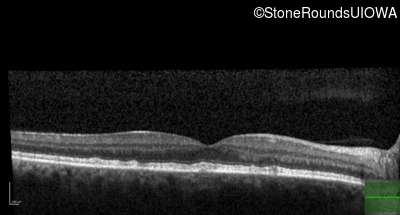

Age at visit: 49 years

This 49 year old man was first told he had a fundus abnormality on a routine eye exam at age 34. Ten years later he noticed some distortion just superior to fixation.

Pattern Dystrophy PRPH2 Gln239Stop CAG>TAG   AD